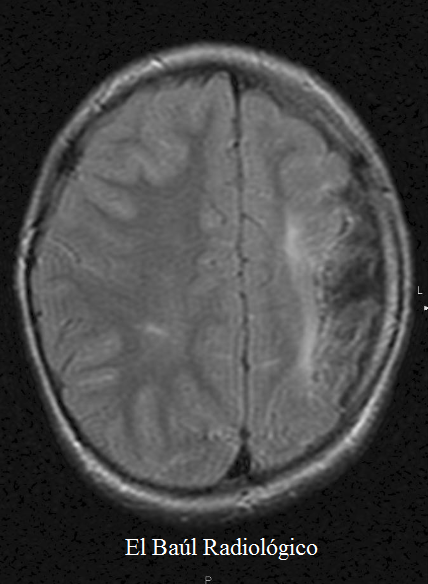

Hay otros procesos patológicos caracterizados por una asimetría en el tamaño de ambos hemisferios cerebrales, sin disgenesia de la corteza cerebral, (pseudo-hemimegalencefalia)(Figura 1) que, por ese motivo, no deben confundirse con la hemimegalencefalia disgenésica porque la evolución clínica y el pronóstico son diametralmente opuestos, en ambos casos.

FIGURA 1) Imagen STIR-T2. En proyección coronal, se aprecia una clara asimetría de volumen entre el hemisferio cerebral derecho, más grande, y el izquierdo. Esta pseudo-hemimegalencefalia (es mejor no utilizar este término para evitar confusiones) es debida a la reducción de volumen del hemisferio izquierdo, como consecuencia de un infarto en el territorio de la arteria cerebral media izquierda, ocurrido durante el periodo intrauterino.